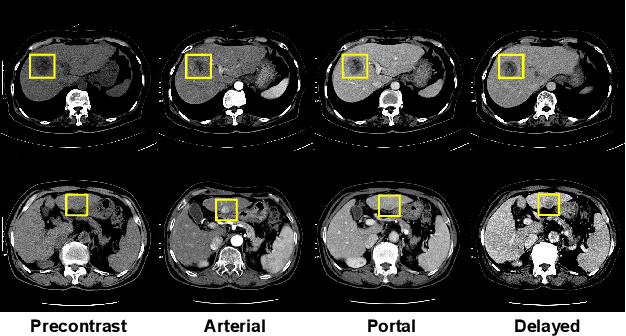

Abstract:The computer-aided diagnosis of focal liver lesions (FLLs) can help improve workflow and enable correct diagnoses; FLL detection is the first step in such a computer-aided diagnosis. Despite the recent success of deep-learning-based approaches in detecting FLLs, current methods are not sufficiently robust for assessing misaligned multiphase data. By introducing an attention-guided multiphase alignment in feature space, this study presents a fully automated, end-to-end learning framework for detecting FLLs from multiphase computed tomography (CT) images. Our method is robust to misaligned multiphase images owing to its complete learning-based approach, which reduces the sensitivity of the model's performance to the quality of registration and enables a standalone deployment of the model in clinical practice. Evaluation on a large-scale dataset with 280 patients confirmed that our method outperformed previous state-of-the-art methods and significantly reduced the performance degradation for detecting FLLs using misaligned multiphase CT images. The robustness of the proposed method can enhance the clinical adoption of the deep-learning-based computer-aided detection system.

Abstract:We present a focal liver lesion detection model leveraged by custom-designed multi-phase computed tomography (CT) volumes, which reflects real-world clinical lesion detection practice using a Single Shot MultiBox Detector (SSD). We show that grouped convolutions effectively harness richer information of the multi-phase data for the object detection model, while a naive application of SSD suffers from a generalization gap. We trained and evaluated the modified SSD model and recently proposed variants with our CT dataset of 64 subjects by five-fold cross validation. Our model achieved a 53.3% average precision score and ran in under three seconds per volume, outperforming the original model and state-of-the-art variants. Results show that the one-stage object detection model is a practical solution, which runs in near real-time and can learn an unbiased feature representation from a large-volume real-world detection dataset, which requires less tedious and time consuming construction of the weak phase-level bounding box labels.